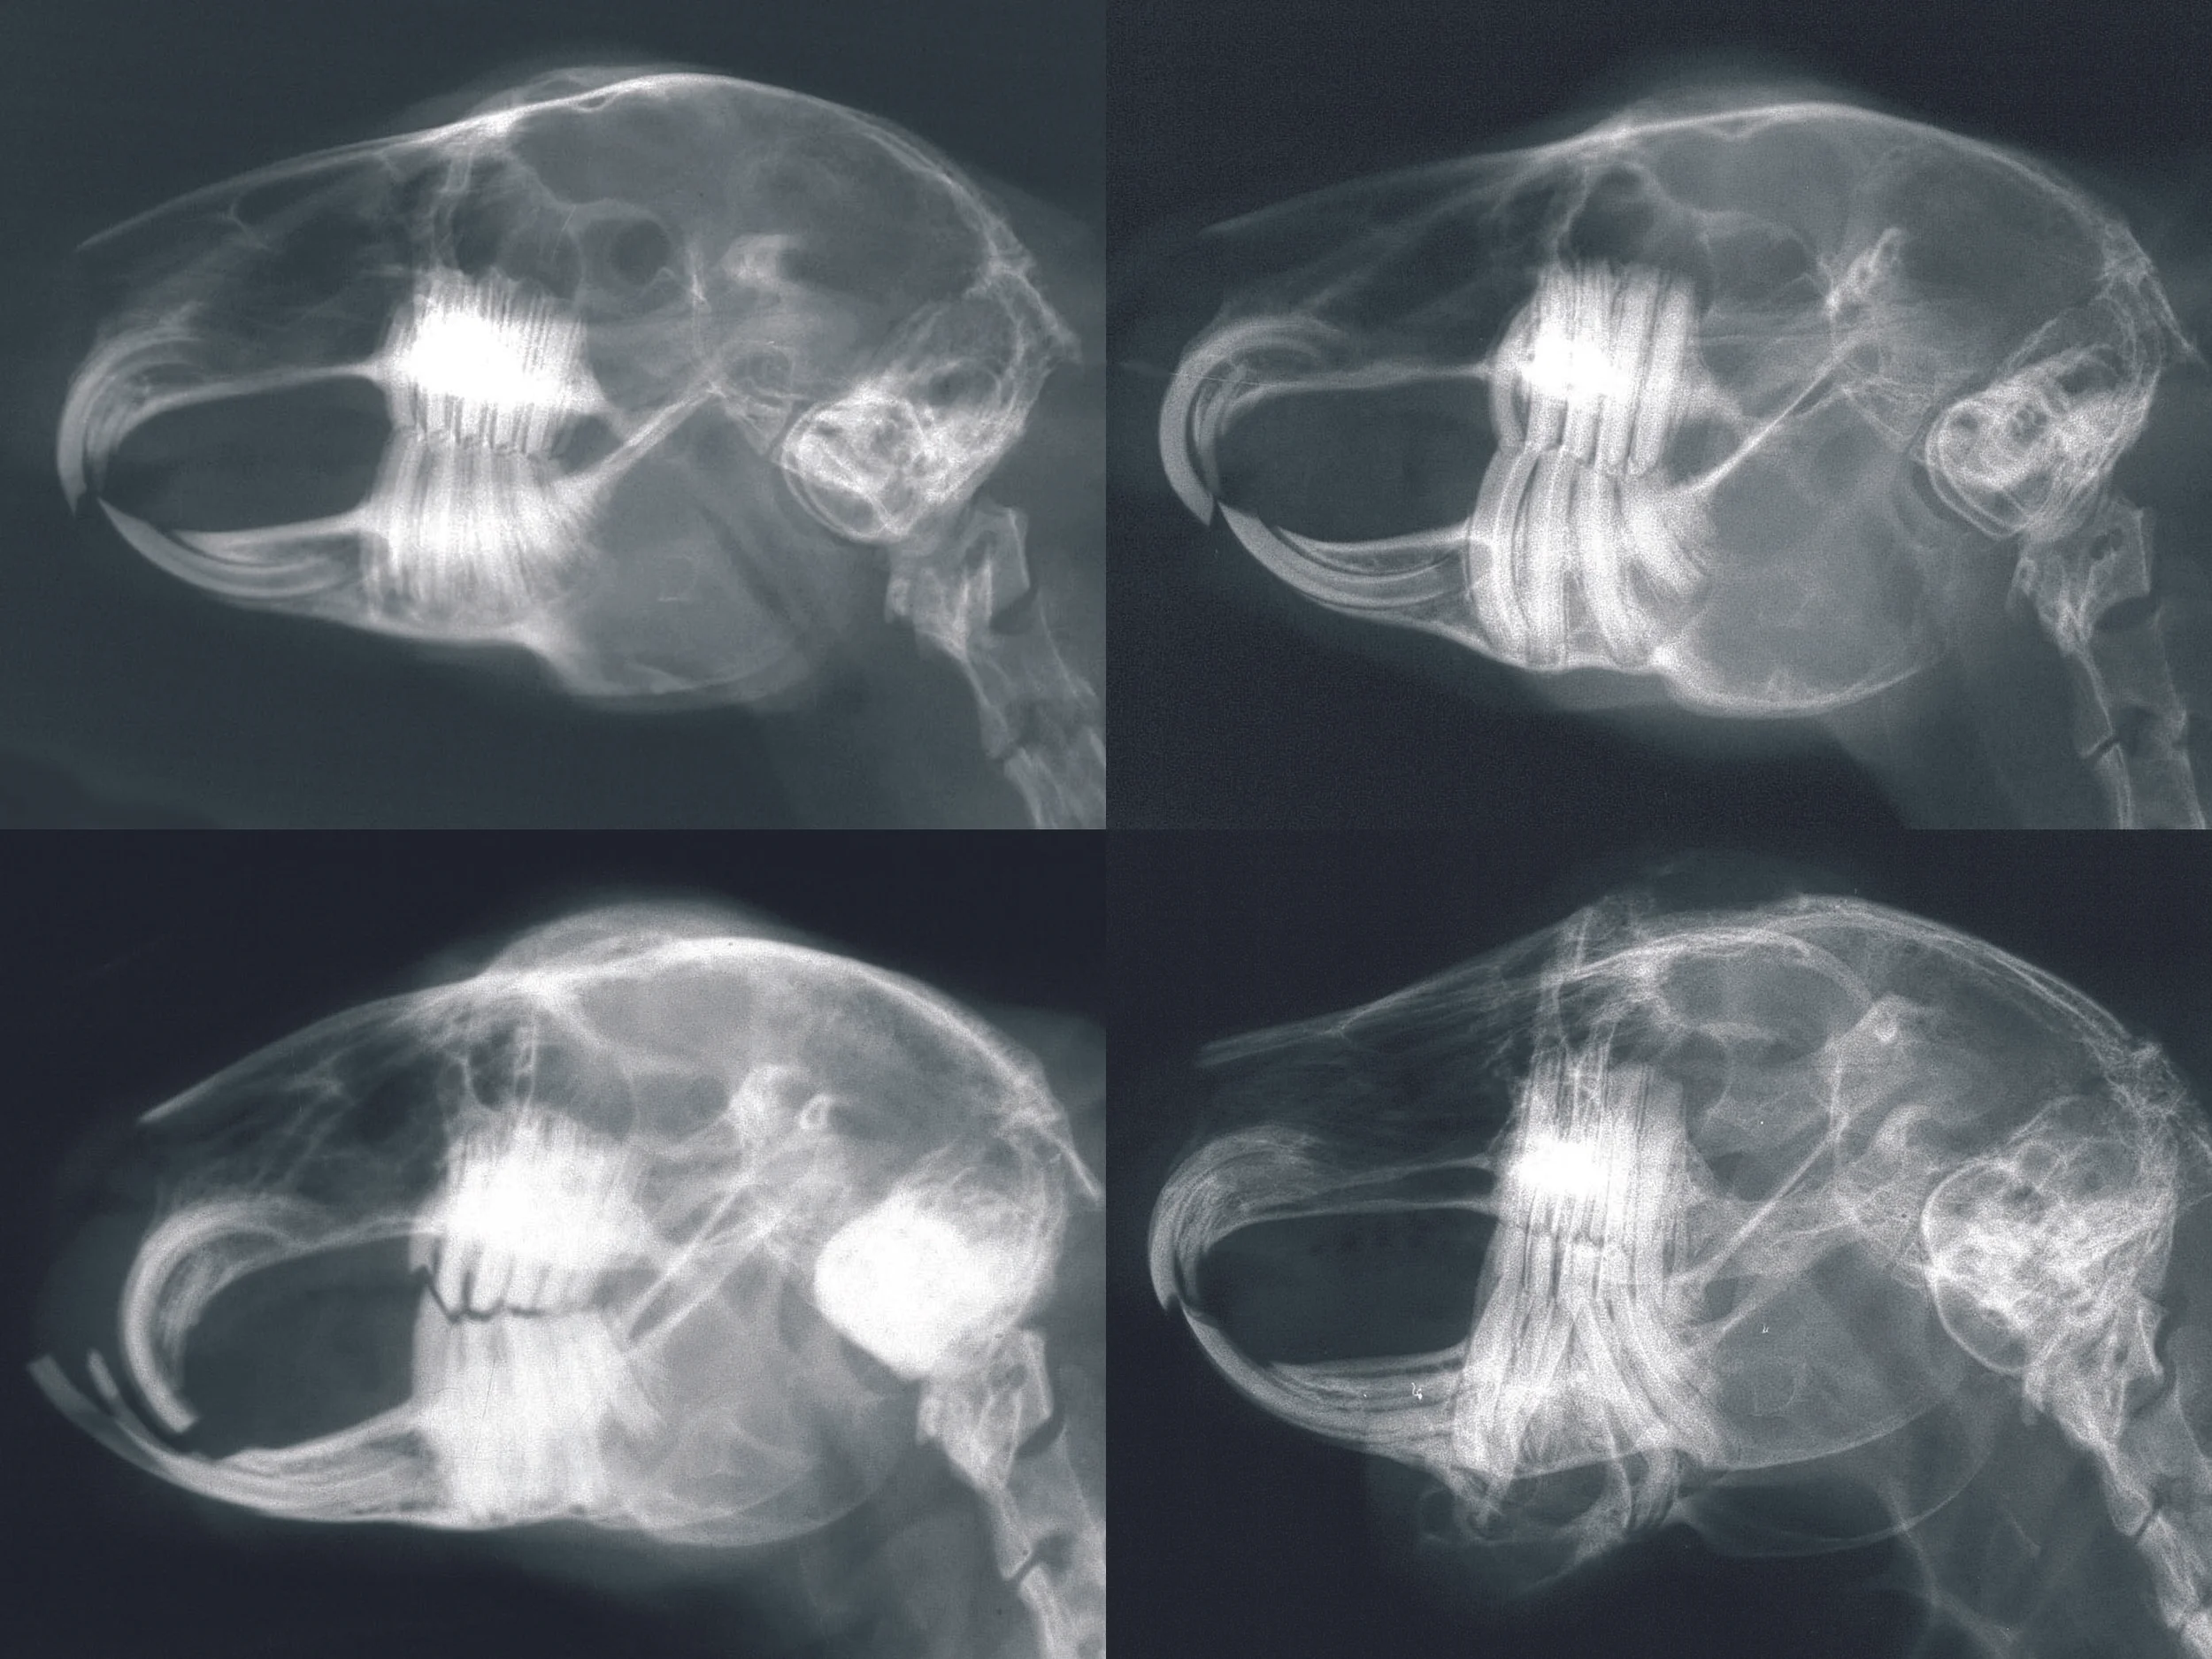

2. Dental Disease

Dental disease can be mild to severe, and if not treated always gets worse. Rabbit teeth grow continually, and any condition that interferes with perfect tooth alignment results in dental disease, which is painful, and interferes with the ability to eat.

Causes: currently under debate; theories include injuries, dietary causes and genetics

Prognosis: Good to excellent when managed properly.

Treatment: Periodic adjustments of tooth length and shape, and treatment of any secondary problems, such as infection and discomfort.

Dental disease can be a "stealthy" disease, and many times signs are vague and don't appear related to teeth. Call right away if your rabbit seems "off".